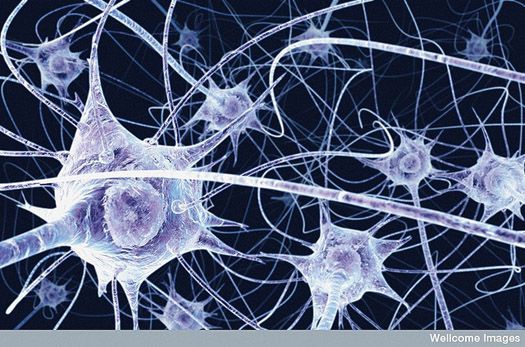

Specialised nerve endings & cells related to sexual function

Medical scientists and pathologist have been able to identify a number of highly specialised nerve endings and specialised cells related to sexual function. It is proposed that these nerve endings help with maintaining stimulation and erection. It is commonly reported by circumcised men (being circumcised an adult) that they find it difficult to maintain stimulation and an erection compared to previous experience with a foreskin. The loss of the foreskin results in a very significant loss of nerve endings which has been shown to significantly reduce the perception of sensitivity during sexual activity.

We undertook further research and received significant data that supported the observation that the foreskin plays a vital role in providing a lubricating interface between the penis and the vagina. The loss of the foreskin during intercourse can be described as like sticking a pole in to the vagina and moving it back and forth causing abrasion. The foreskin behaves much like a cushion of skin that prevents abrasion and allows for the extremely sensitive nerve cells to send very positive and rewarding messages back to the brain. Men without a foreskin require extra personal lubricant to reduce the abrasion on their partner. We recommend to only use a lubricant formulated to add extra protection to your partner.